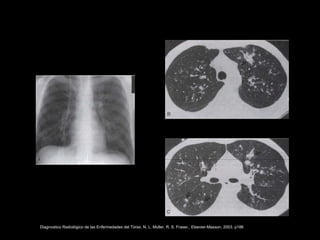

Spectrum of Pulmonary Aspergillosis: Histologic, Clinical, and Radiologic Findings

Tomás Franquet, Nestor L. Müller, Ana Giménez, Pedro Guembe, Jesus de la Torre, and S. Bagué

RadioGraphics 2001 21:4, 825-837

Diagnostico Radiológico de las Enfermedades del Tórax. N. L. Muller, R. S. Fraser,. Elsevier-Masson, 2003. p186

ASPERGILOSIS INVASIVA • Pacientesneutropénicos. • SIDA. • Manifestaciones clínicas: • Traqueobronquitis. • Bronquiolitis. • Bronconeumonía. Spectrum of Pulmonary Aspergillosis: Histologic, Clinical, and Radiologic Findings Tomás Franquet, Nestor L. Müller, Ana Giménez, Pedro Guembe, Jesus de la Torre, and S. Bagué RadioGraphics 2001 21:4, 825-837

Spectrum of PulmonaryAspergillosis: Histologic, Clinical, and Radiologic Findings Tomás Franquet, Nestor L. Müller, Ana Giménez, Pedro Guembe, Jesus de la Torre, and S. Bagué RadioGraphics 2001 21:4, 825-837

Diagnostico Radiológico delas Enfermedades del Tórax. N. L. Muller, R. S. Fraser,. Elsevier-Masson, 2003. p186